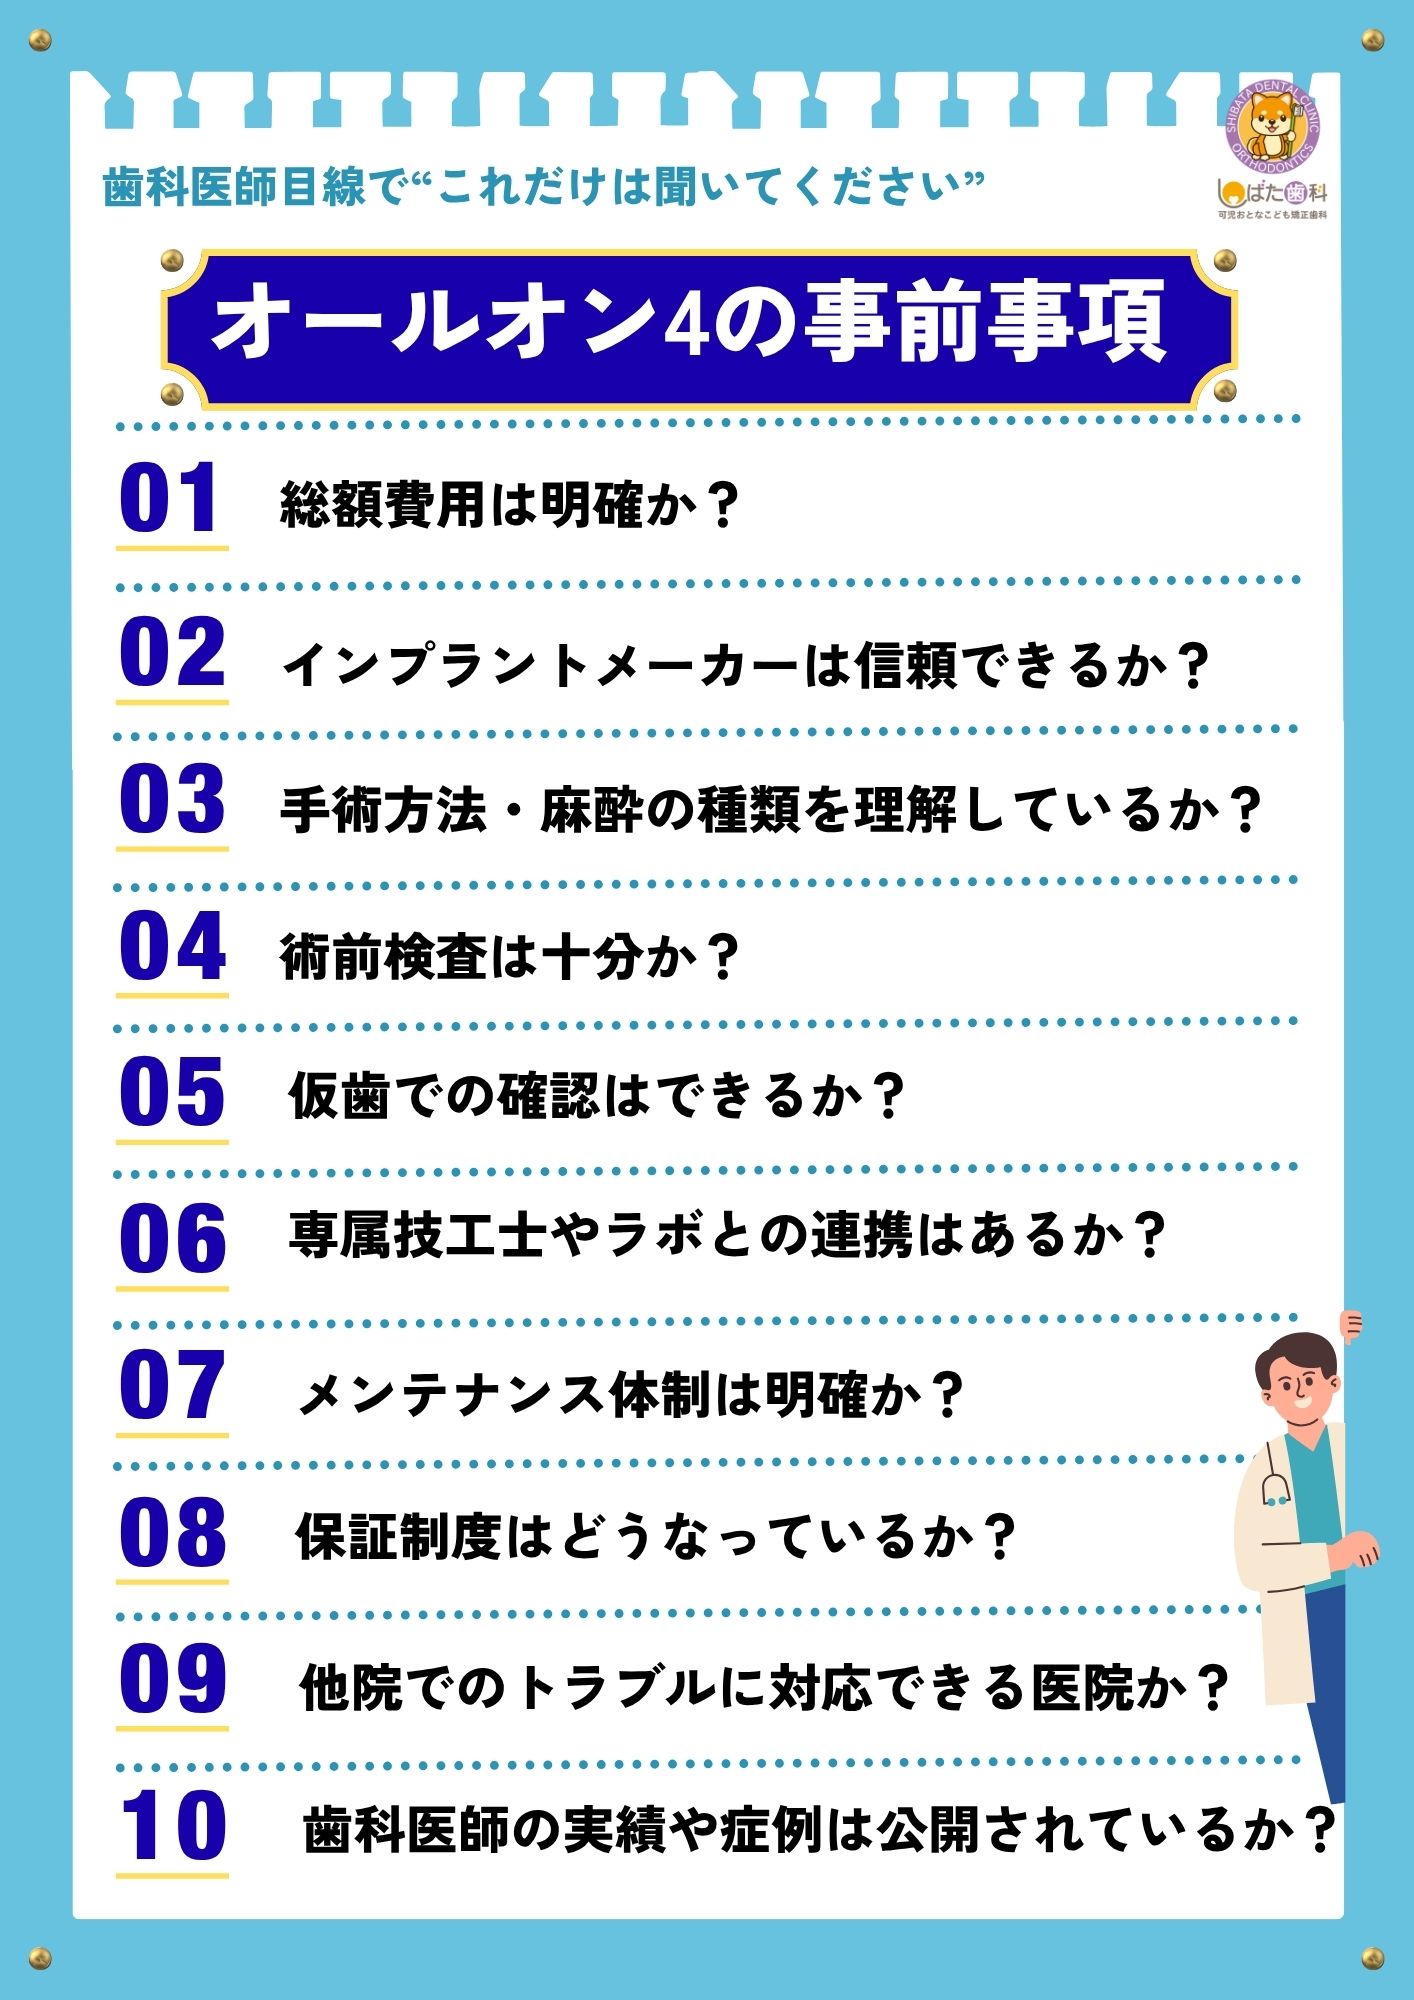

このブログでは、後悔しないために患者さんが事前に確認すべき10のチェックポイントを、最新の研究データとともに解説します。

その様な過去の経験を踏まえ、当院ではオールオンフォー治療を受けられる方や、検討される方には「治療前に確認すべき10のチェックポイント」として「こんなはずじゃなかった」と後悔しないためにも、事前に知っておくべきポイントを歯科医師目線で挙げてみました。

◉確認すべき10のチェックポイント

① 総額費用は明確か?

「100万円〜」と広告されていても、検査・麻酔・仮歯・保証が別料金の場合があります。すべての処置をした場合の総額の見積りを必ず確認しましょう。

また、オールオンフォーの毎メンテンス料金や仮歯のやりかえ代金、本歯が消耗した場合の作り替え代金等の付随費用も確認しておきましょう。

② インプラントメーカーは信頼できるか?

世界的に長期使用実績のあるメーカーかどうか。安価なノーブランドでは、将来的なパーツ供給が難しくなる可能性があります。

③ 手術方法・麻酔の種類を理解しているか

④ 術前検査は十分か?

⑤ 仮歯での確認はできるか?

⑥ 専属技工士やラボとの連携はあるか?

⑦ メンテナンス体制は明確か?

⑧ 保証制度はどうなっているか?

⑨ 他院でのトラブルに対応できる医院か?

⑩ 歯科医師の実績や症例は公開されているか?